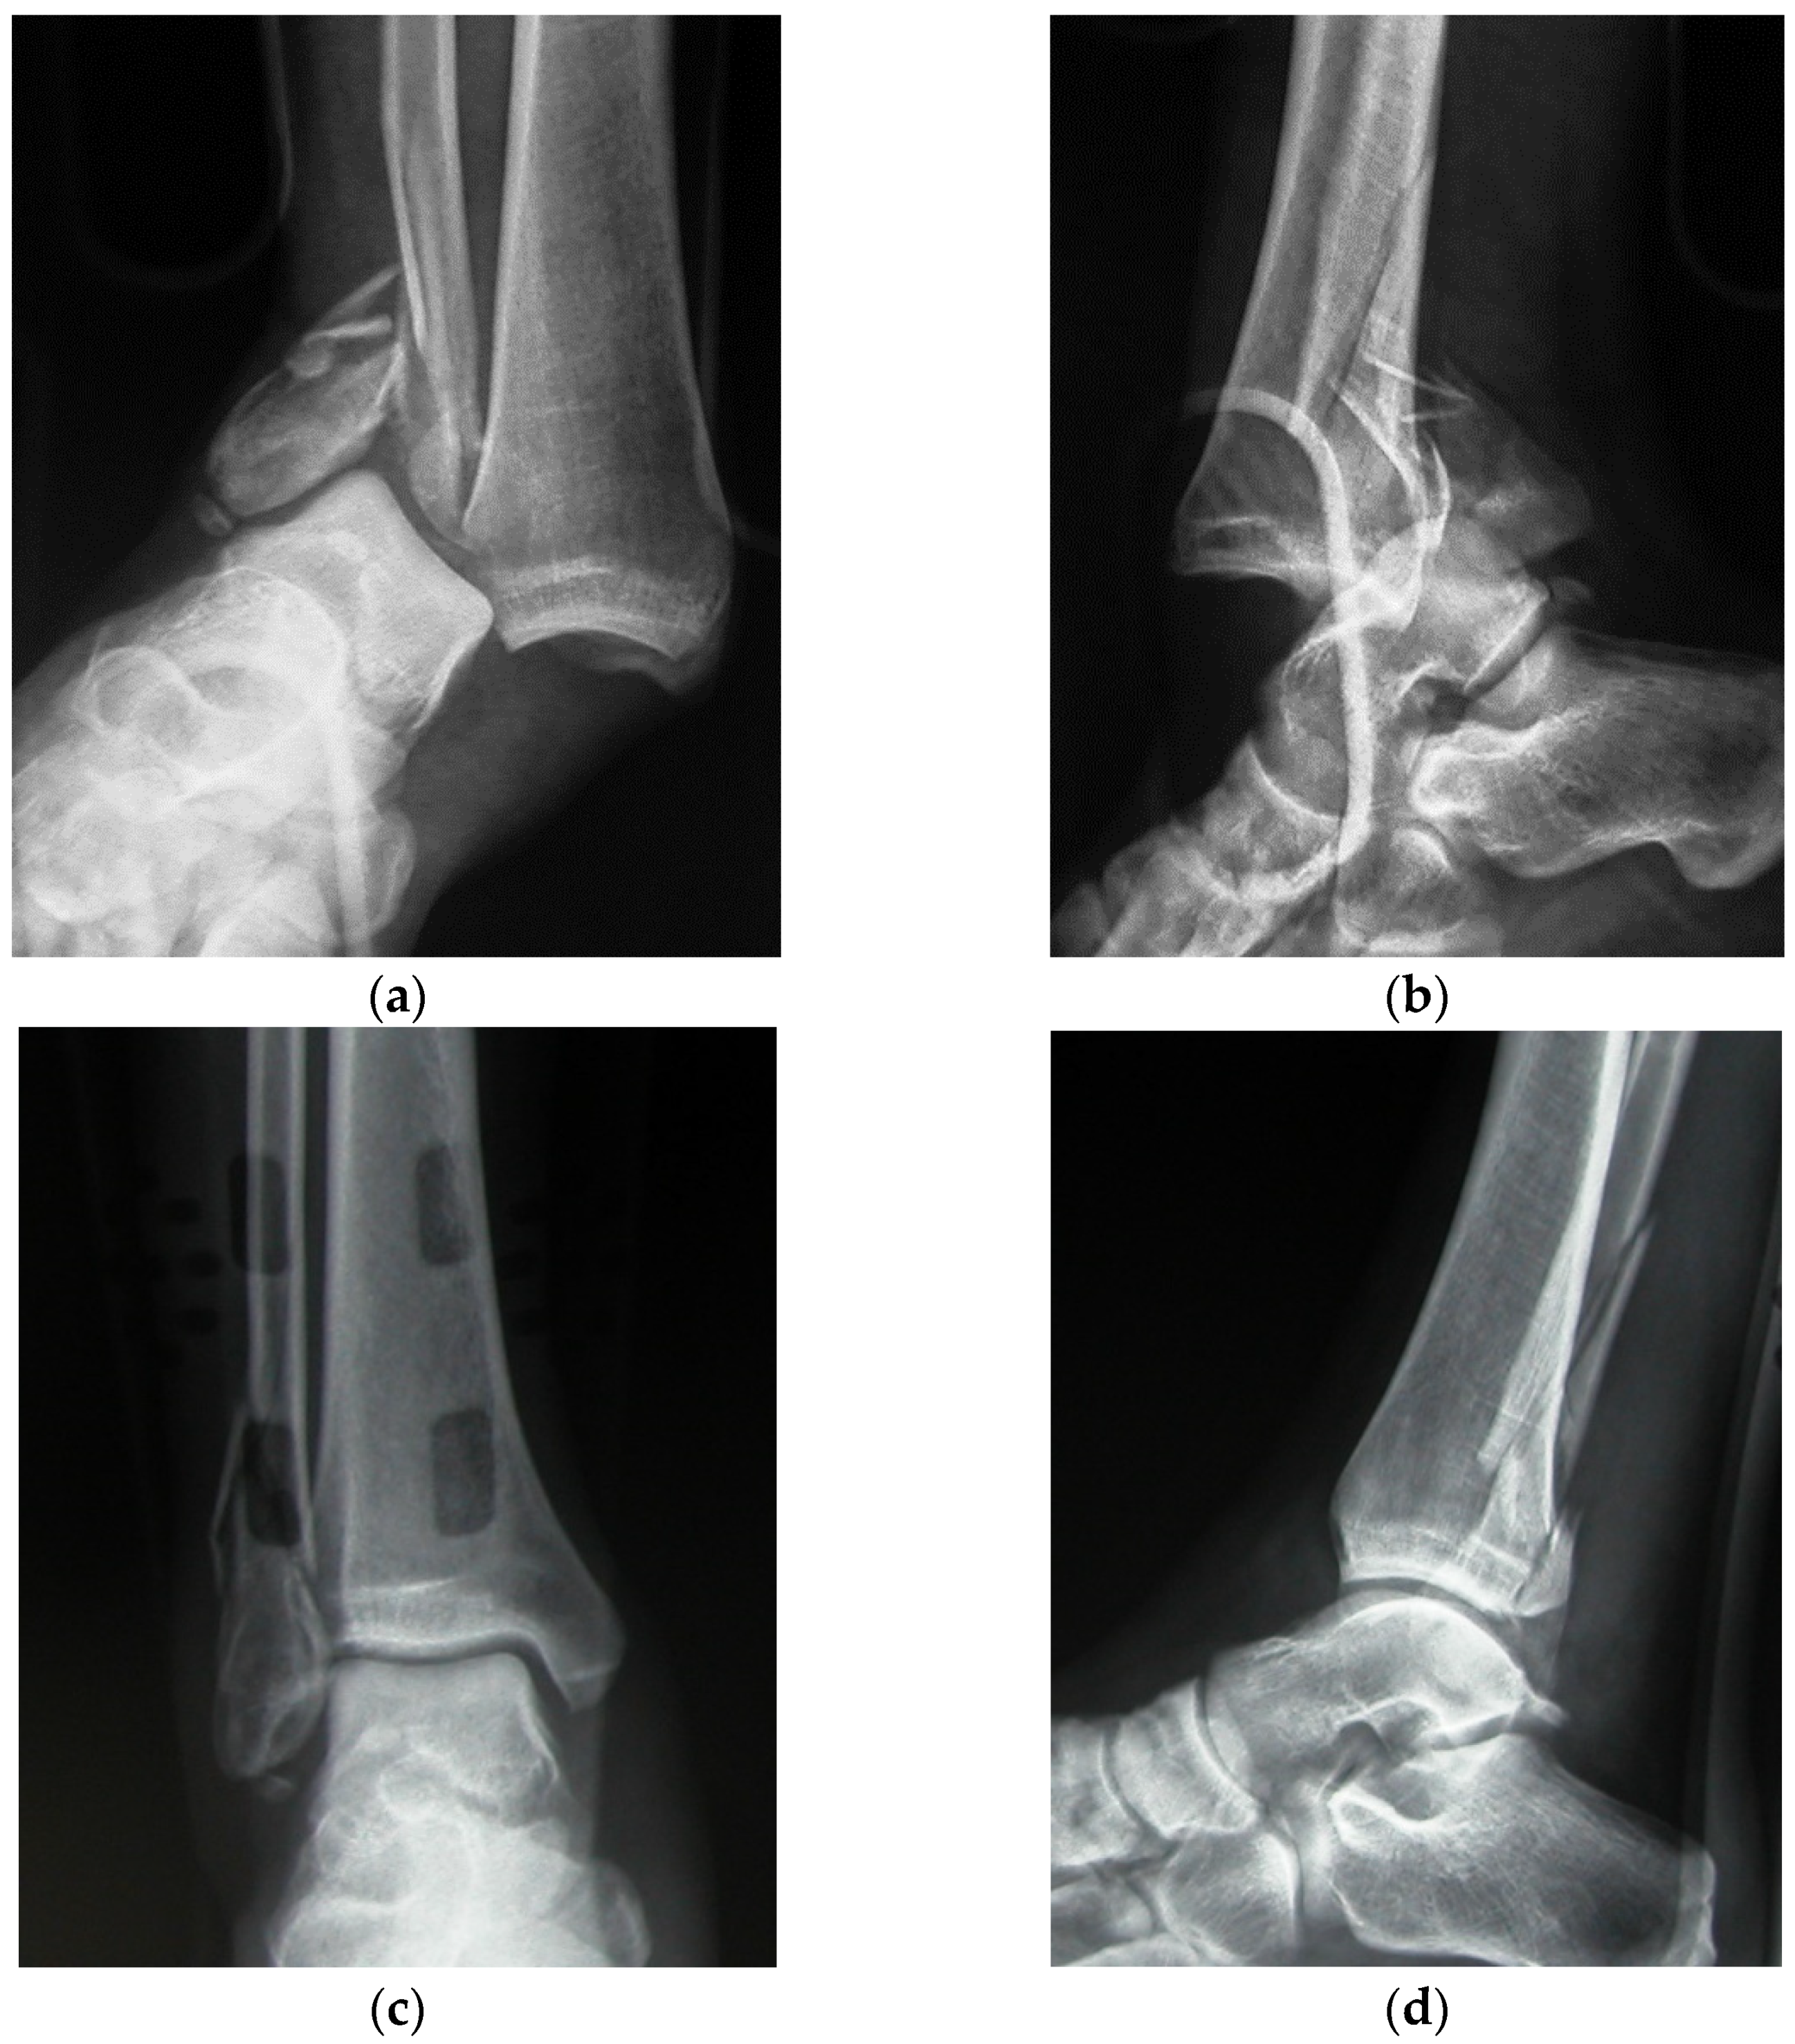

2. Materials and Methods

3. Results